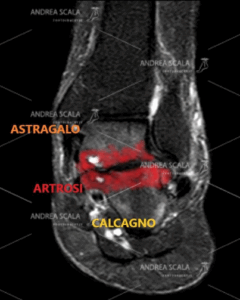

L’articolazione tra astragalo e calcagno in un piede pronato valgo è deviata, ha lavorato male e si è consumata. E’ presente la degenerazione della cartilagine articolare, le ossa si toccano, c’è l’artrosi e c’è molto dolore. Sarebbe stato meglio operare prima.